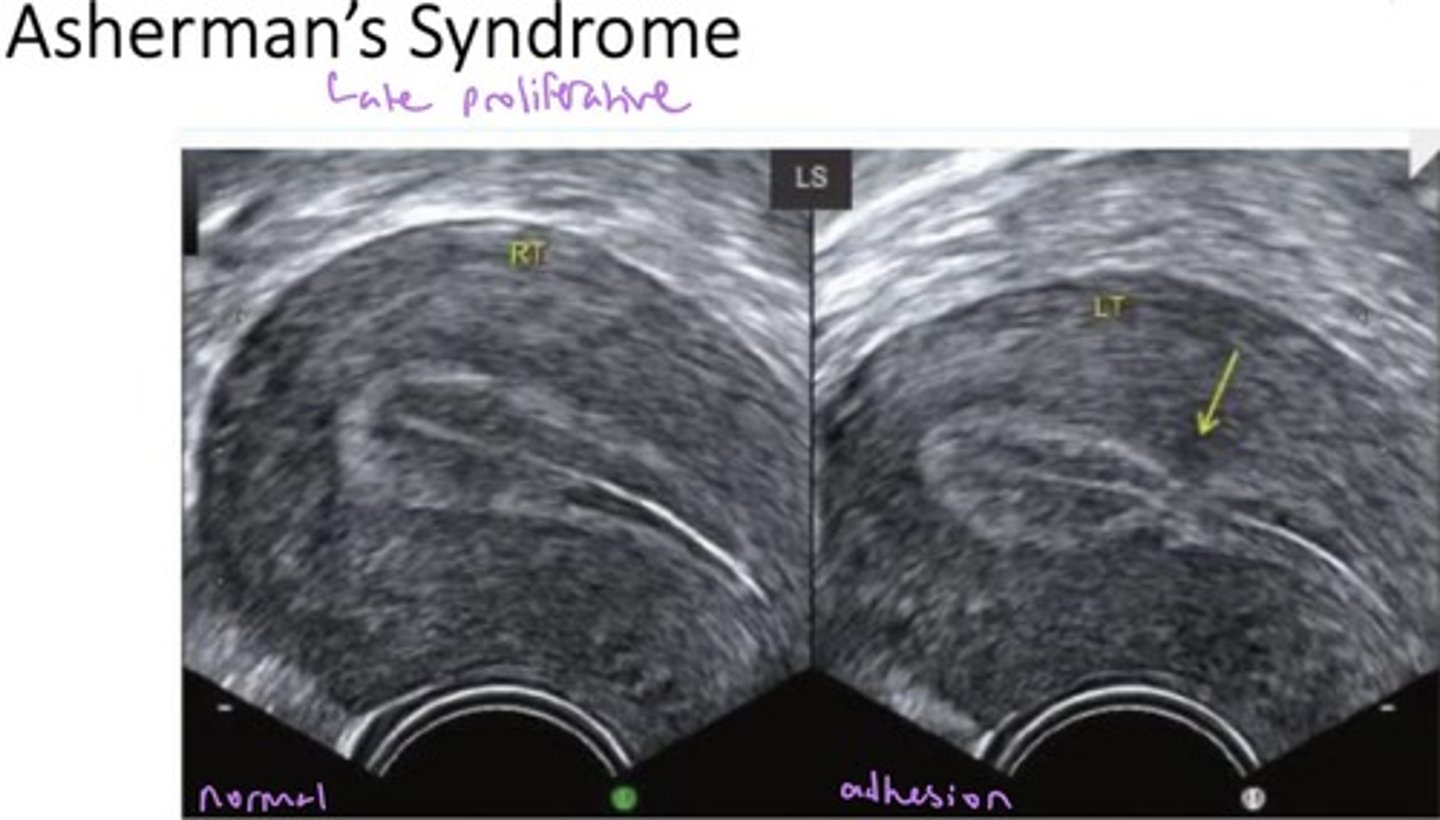

What does Asherman's syndrome look like sonographically?

- Hypoechoic breaks in endometrial continuity

- May calcify = echogenic

- W/ coexistent fibrosis = echogenic

- Endo pockets w/ loculated fluid

How do adhesions appear on SIS?

Adhesions appear as echogenic bands